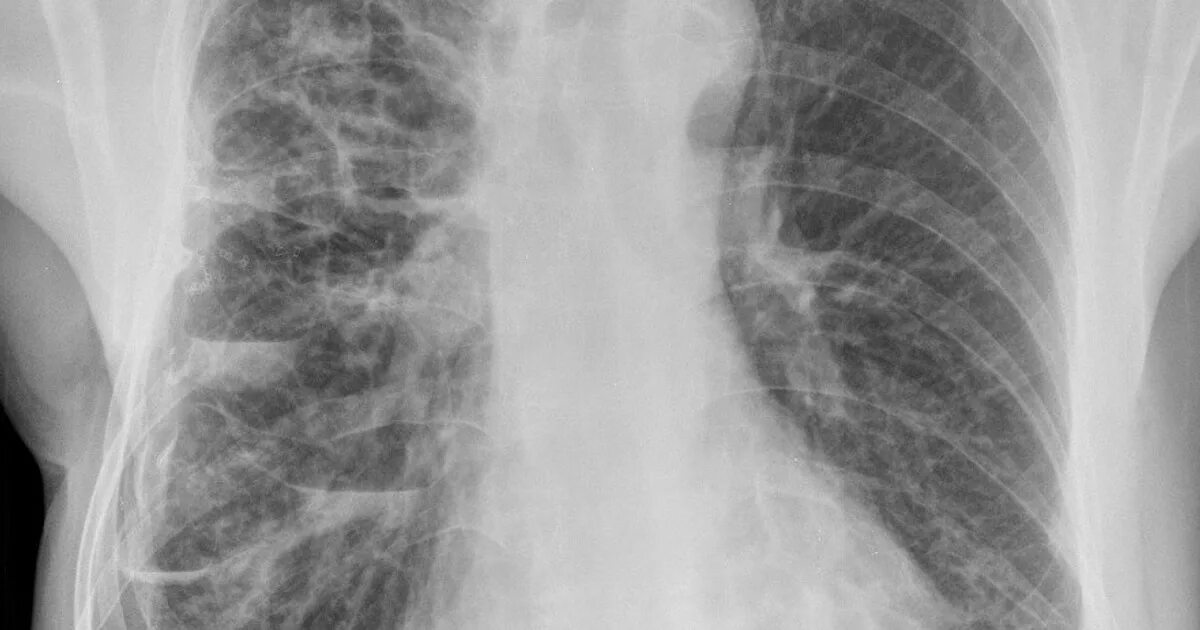

Бронхоэктазия